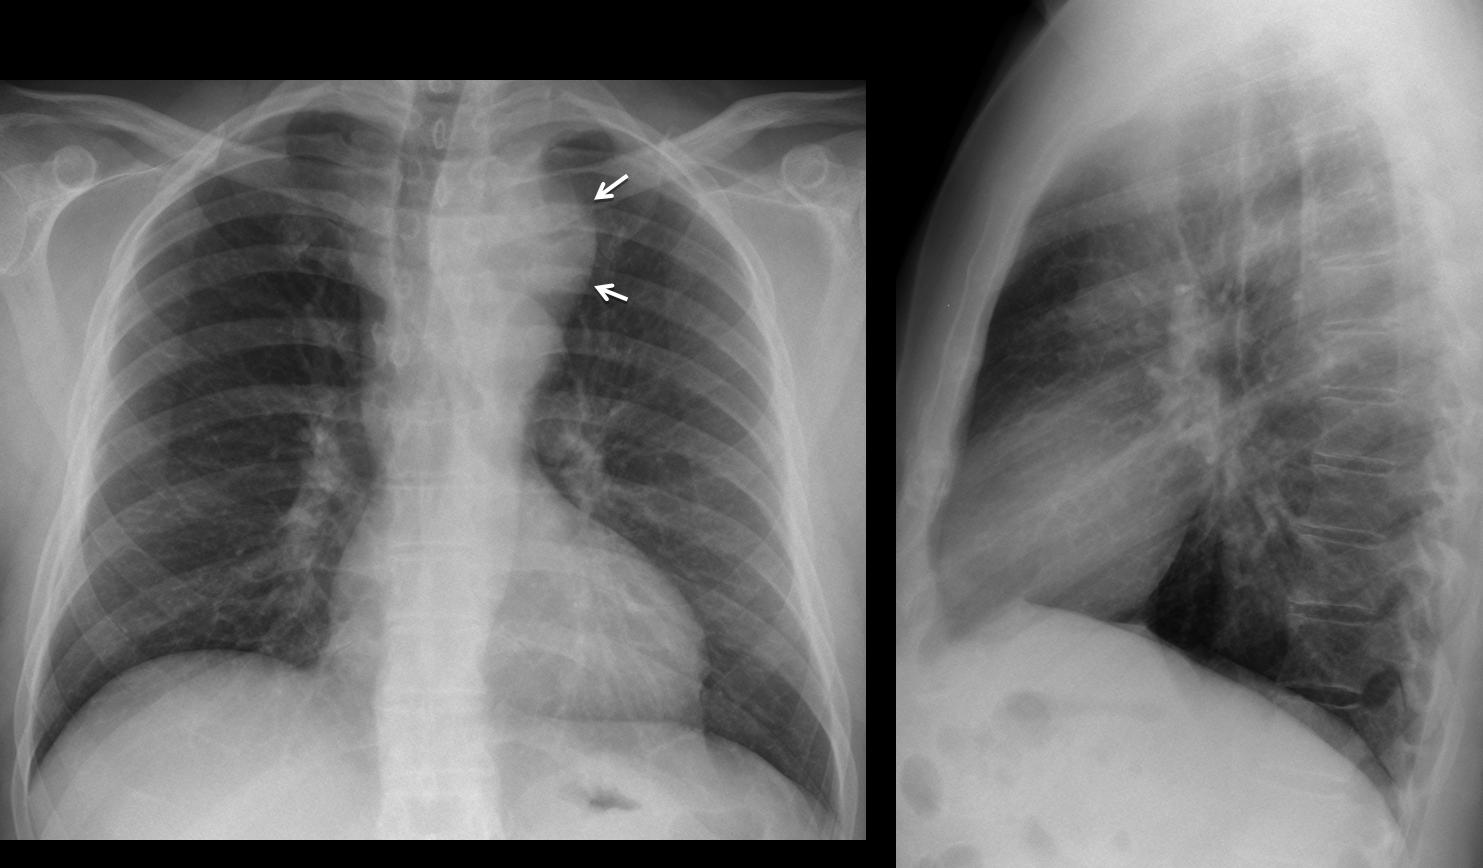

Phình ĐM chủ

Phình ĐM chủ - Ảnh 2

» Thông tin: Nam giới – 45 tuổi.

» Lâm sàng: Đau ngực.